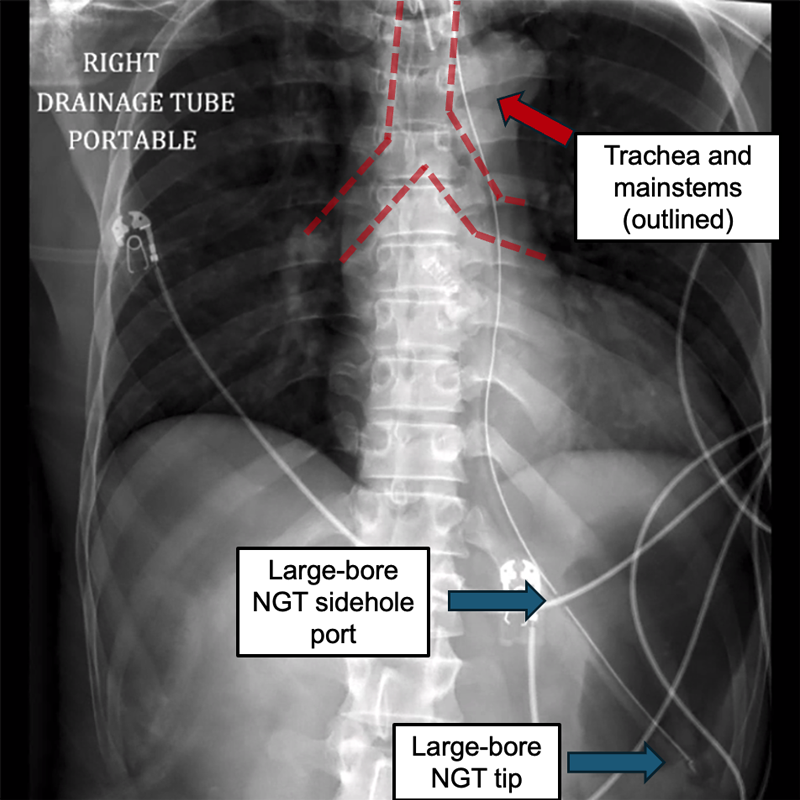

A large-bore NGT is placed. Is placement confirmed?

Correct! We can see the large-bore NGT bisect the left mainstem bronchus, course through the G-E junction, and finally pass much below the diaphragm. Because this is a large-bore tube, we also have to pay attention to the location of the sidehole port. We can also see here that the sidehole port also goes past the G-E junction and is itself below the diaphragm and in the stomach. This tube can now be used.